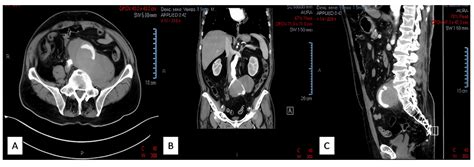

Diagnosing an Iliac Artery Aneurysm typically involves a combination of medical history, physical examination, and imaging tests. The diagnostic process may include:

• Computed Tomography Angiography (CTA): This imaging test provides detailed images of the blood vessels and can help determine the size and location of the aneurysm.